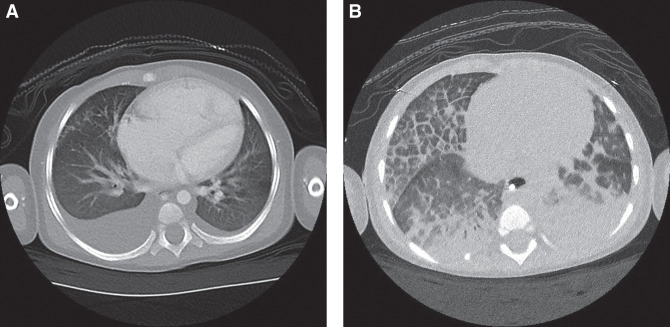

Alveolar capillary dysplasia (ACD) is a fatal disorder that typically presents in the neonatal period with refractory hypoxemia and pulmonary hypertension. Lung biopsy is traditionally required to establish the diagnosis. We report a 22-mo-old male who presented with anemia, severe pulmonary hypertension, and right heart failure. He had a complicated hospital course resulting in cardiac arrest and requirement for extracorporeal membrane oxygenation. Computed tomography of the chest showed a heterogenous pattern of interlobular septal thickening and pulmonary edema. The etiology of his condition was unknown, lung biopsy was contraindicated because of his medical fragility, and discussions were held to move to palliative care. Rapid whole-genome sequencing (rWGS) was performed. In 2 d it resulted, revealing a novel FOXF1 gene pathogenic variant that led to the presumptive diagnosis of atypical ACD. Cases of atypical ACD have been reported with survival in patients using medical therapy or lung transplantation. Based on the rWGS diagnosis and more favorable potential of atypical ACD, aggressive medical treatment was pursued. The patient was discharged home after 67 d in the hospital; he is currently doing well more than 30 mo after his initial presentation with only one subsequent hospitalization and no requirement for lung transplantation. Our case reveals the potential for use of rWGS in a critically ill child in which the diagnosis is unknown. rWGS and other advanced genetic tests can guide clinical management and expand our understanding of atypical ACD and other conditions.